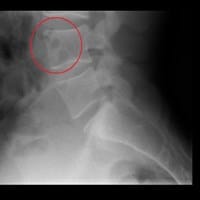

Radiografía normal ? Manchas negras que son ?

Resulta que estoy un poco inquieto y preocupado debido a que me mandaron a sacar unos rayos X lumbares pero revisándolos observe esas manchas negras en una vertebra, al parecer y por lo que he visto en varios lados es aire o burbujas de gas, quisiera...